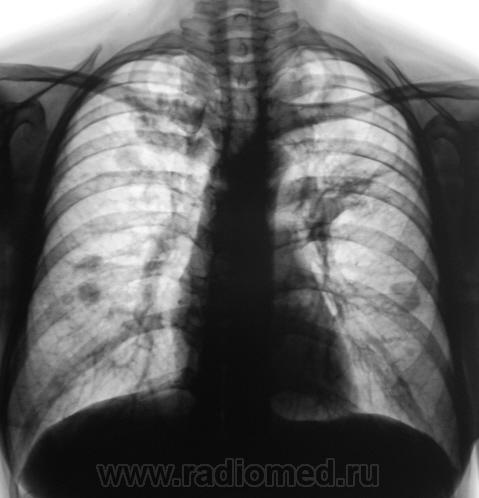

2010 г.

Нужно дифференцировать, исход диссеменированного туберкулёза ( в 2008г.) в множественные туберкулёмы в 2010г, и MTS в лёгкие с некоторой положительной димамикой, возможно на фоне проведённой химеотерапии (нужен анамнез!).

Возможно вы правы, но может быть просто, проявлением лечённого диссеминированного туберкулёза лёгких в динамике.

Сочетанная - что (понятно) с чем? Микст чего?